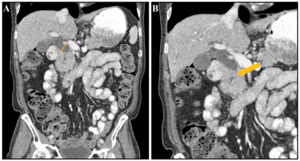

A 77-year-old male with a past medical history of rectal adenocarcinoma treated with chemoradiation and total proctectomy complicated by a colocutaneous fistula requiring colostomy and suppressive antibiotics (cefdinir 300mg, metronidazole 250mg) was referred to the emergency department by his rheumatologist for elevated liver function tests (Aspartate aminotransferase (AST) 417 U/L, Alanine aminotransferase (ALT) 409 U/L, Alkaline phosphatase (ALP) 730 U/L) on routine outpatient labs. His medical conditions further included recently diagnosed type 2 diabetes treated with metformin and Sjogren’s disease, not currently on treatment. On presentation, the patient was asymptomatic and vital signs demonstrated a temperature of 36.7°C, blood pressure of 137/80 mm Hg, heart rate of 86 beats/min, respiratory rate of 12 breaths/min, and O2 saturation of 98% on room air. On examination, he had an intact colostomy, and his abdomen was non-tender and without appreciable masses. No rashes, petechiae, or jaundice were noted. Computed tomography (CT) of the abdomen demonstrated a severely dilated common bile duct, with a possible stricture versus mass noted at the mid-distal common bile duct (Figure 1).